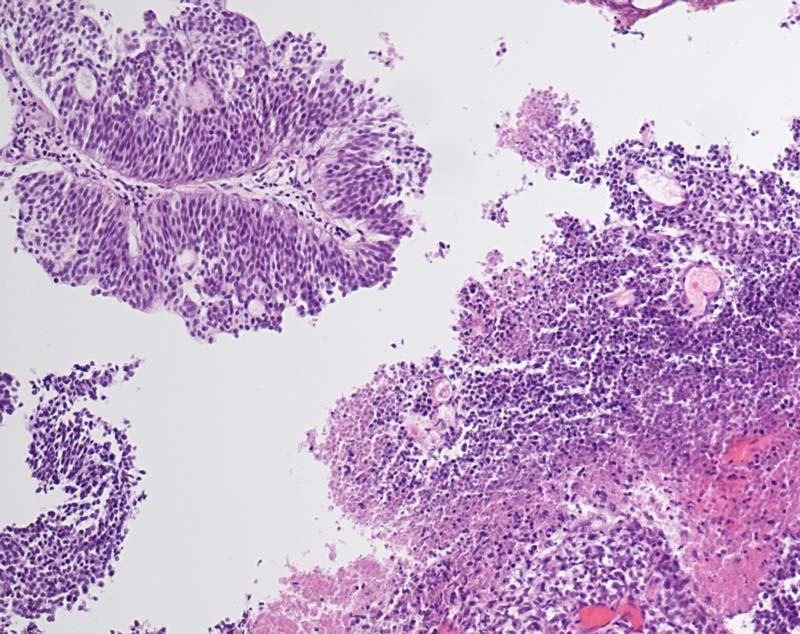

Kleinzelliges Harnblasenkarzinom

Die vorliegende Tumor ist ungewöhnlich. Offenbar bestehen zwei sehr unterschiedliche Tumorkomponenten. (Kombiniertes Harnblasenkarzinom)

1. Findet sich ein typisches papilläres Urothelkarzinom mit mässiggradiger Epitheldysplasie (und einer fokalen adenomatösen Differenzierung).

2. Finden sich mehrere kleine Fragmente von teils nekrotischem Tumorgewebe mit kleinzelligem Aspekt entsprechend einem kleinzelligen Karzinom.

Erstbefund Blasentumor linke Seitenwand bis Blasenhals, Ummauerung Ostium und Nierenabflussbehinderung. Breitbasig, teils papillär, tief solide erscheinend.

Rein kleinzellige Karzinome sind selten (weniger als 0.5% der Harnblasentumoren). In der Hälfte der Fälle liegen gemischte Tumoren mit kleinzelliger Komponente vor. Die meisten Patienten haben bei Diagnose grosse tief invasive Tumoren und oft bereits Metastasen in Lymphknoten, Knochen und Leber.